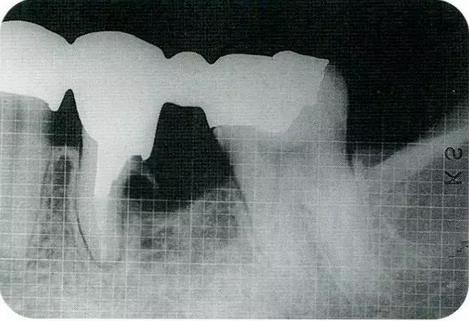

▼圖20-1

圖20-1術(shù)前X光片

▼圖20-2

圖20-2術(shù)前,左上7的牙冠明顯崩壞,齲壞已經(jīng)達(dá)到牙齦下緣深處。在進(jìn)行治療前盡可能的將軟化牙質(zhì)去除。